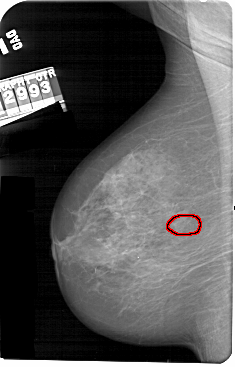

A_1565_1.LEFT_CC

LEFT_CC LINES 5446 PIXELS_PER_LINE 3196 BITS_PER_PIXEL 12 RESOLUTION 43.5 OVERLAY

FILE: A_1565_1.LEFT_CC.OVERLAY

TOTAL_ABNORMALITIES 1

ABNORMALITY 1

LESION_TYPE CALCIFICATION TYPE AMORPHOUS DISTRIBUTION CLUSTERED

ASSESSMENT 4

SUBTLETY 3

PATHOLOGY BENIGN

TOTAL_OUTLINES 1

BOUNDARY